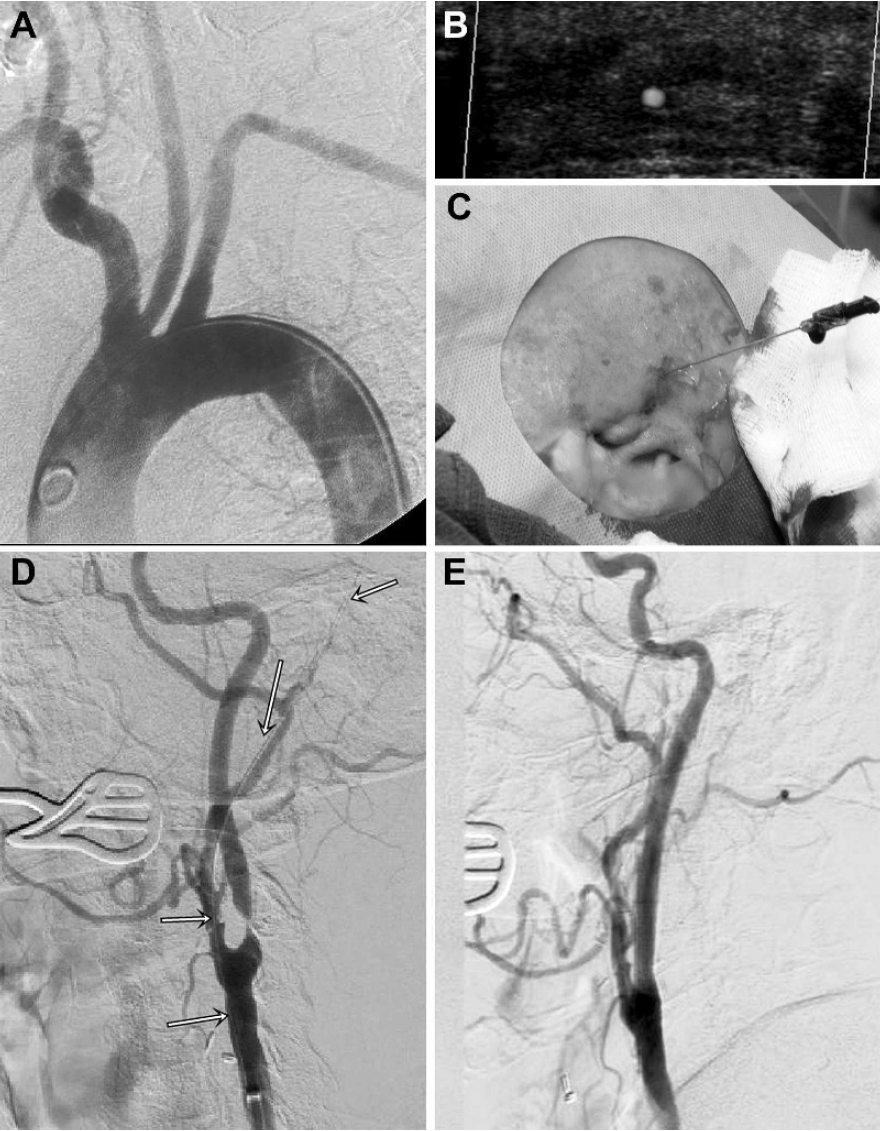

先是造影,发现主动脉弓宽大,L-CCA和主动脉弓的夹角似乎比CTA上看着更加锐利(图2)。

图2. 主动脉弓和左侧颈动脉造影。

图4. 80cm 6F NeuronMax长鞘内衬5F MANI导管。

在260cm加硬泥鳅导丝和MANI导管的同轴引导下,长鞘顺利进入了L-CCA,但过程并不顺利,经历了两次尝试才把它送到狭窄附近。第一次尝试时,加硬导丝和MANI导管上得都不够高;第二次尝试时,加硬泥鳅导丝头端到达了枕动脉的外耳道附近,而MANI导管头端进入了颈外动脉起始段,这才把长鞘带到位。——原来泥鳅导丝可以走那么远!